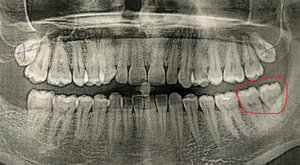

Разошлось мнение двух врачей: одна считает, что кариес на шестнадцатом есть, вторая, что его нет. На рентгене, на шестнадцатом виден темный участок, то есть, скорее кариес есть, чем его нет.

С вашей точки зрения он скорее есть, чем его нет? (речь идет не о поверхностном кариесе, который на рентгене нельзя увидеть, а о более глубоком: среднем или глубоком). Снимок был сделан до лечения.

На снимке в области семнадцатого и двадцать шестого зуба, под пломбой, наблюдается полость, которая неграмотно препарирована перед установкой пломбы, чувствительность и некий дискомфорт при надкусывании или пережевывании твердой пищи связано именно с этим. Что касается шестнадцатого зуба, я считаю, что полость имеется, но все-таки необходим еще и очный прием.